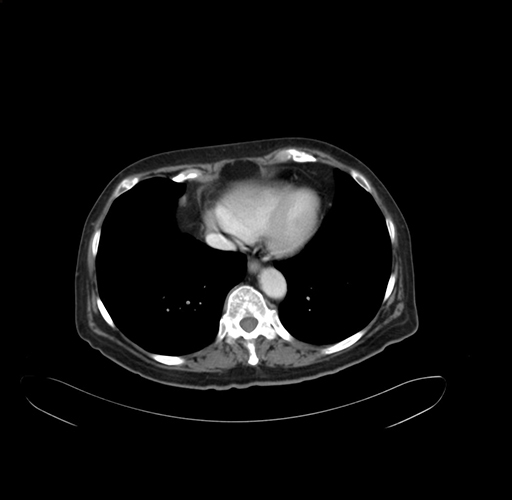

Pre-Chemo: Axial Venous